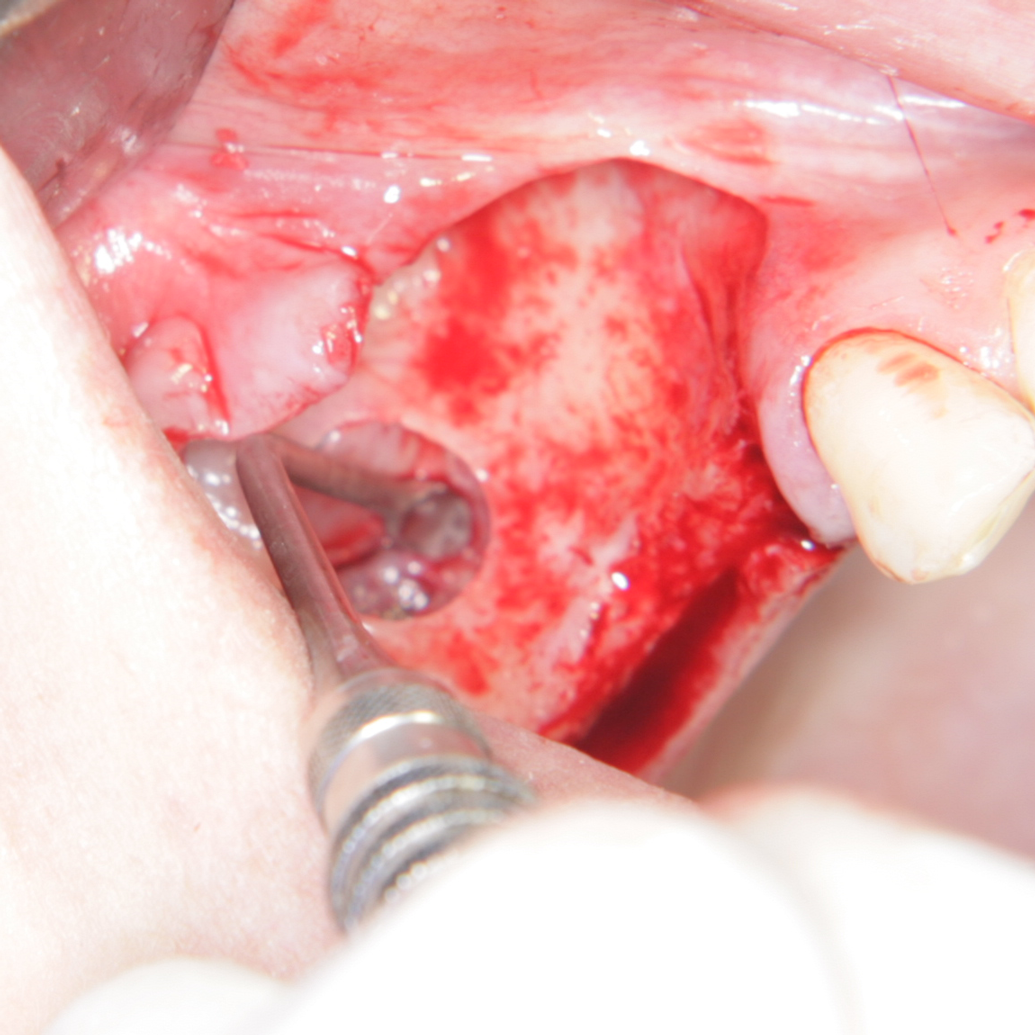

На 24.05.2010 (Денят на Славянската писменост и култура) в град Пловдив беше проведена първа по рода си оперативна интервенция в Република България. Операцията беше изършена в Денталномедицинския отдел на Ралев Дентал АД от екип в състав оператор д-р Венцеслав Ралев и асистент д-р Евгени Миронов (София). Повдигнат беше синусовият под при мъж на възраст 36 години с помощта на пластина от бета-трикалциев фосфат, производство на Casios - Франция. Очакванията на екипа бяха за дълга, тежка и продължителна операция - все пак се извършва нещо, в областта на което никой в България няма опит. Противно на очакванията, интервенцията протече изключително бързо, без никакви усложнения и технически трудности. През 2006 година първият синуслифтинг по открита методика отне на екипа ни около шест часа; описаната тук интервенция започна в 12.15 и само след час и половина (около 13.45 местно време или 11.45 според Гринуич) д-р Ралев обработваше снимките на Photoshop - версия CS3. За обща информация за синуслифтинга посетете тази секция...

Снимка на пластината за повдигане на синусов под. Изработена е от бета-трикалциев фосфат. Производителят е френската компания Касиос. Трикалциевият фосфат е биоактивна калциева сол, която е по-ратворима от хидроксиапатита в биологична среда и много прилича на минералната фаза на човешката кост. Според проучвания от последните години хидроксиапатитът не се резорбира на 100 %, поради което производителят не е включил тази субстанция в състава на пластината Sinus Up. Фабричните размери на пластинката са 40 / 25 мм, нейната дебелина е 2 мм. Обработва се изключително трудно поради голямата твърдост на материала - не се поддава на срязване с ножица или костна клеща, единствено с диамантен пилител е възможно да се оформи според вътрешния контур на синуса. Средната част на пластината е перфорирана с цел по-лесното прорастване на остеобласти и фибробласти, съответно по-бързата остеоинтеграция.